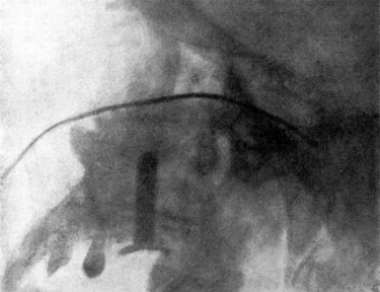

| 333. | Catheterizing the Frontal Sinus | 639 |

| 334. | Radiograph to show the Value of the Röntgen Rays | 639 |

| 335. | Radiograph showing Canula in the Frontal Sinus | 639 |